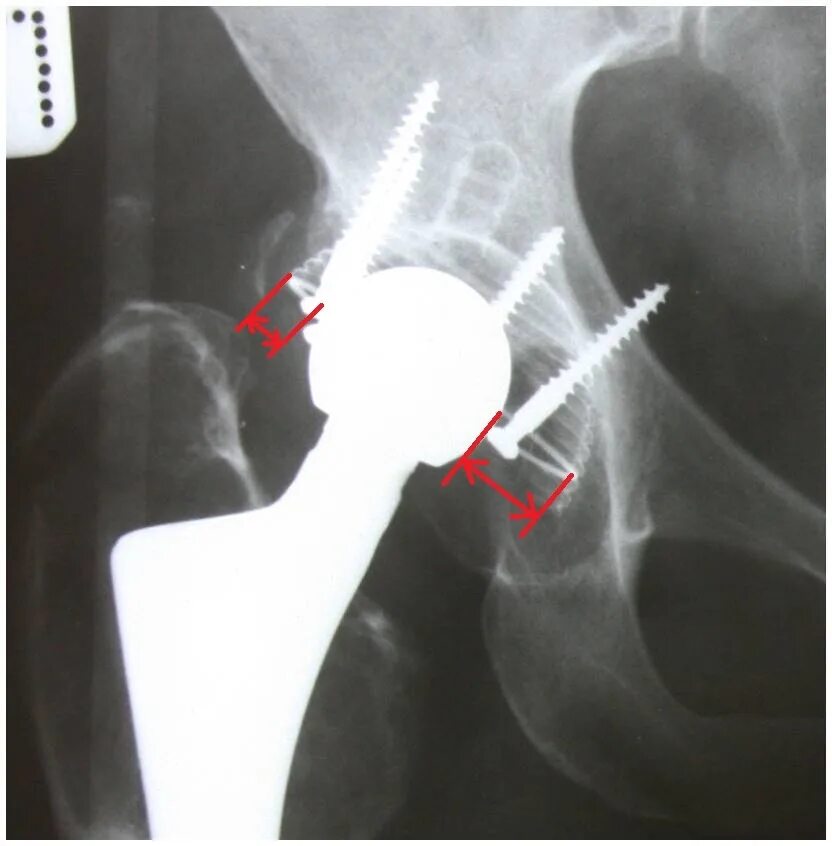

Эндопротез тазобедренного сустава мкб 10